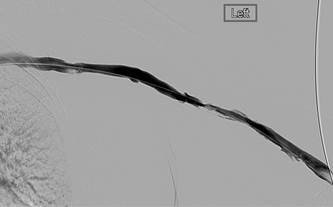

Fistulograma 4 meses después (a).

Fistulograma 4 meses después (b).

Dr. R. Jones, radiólogo intervencionista, Queen Elizabeth Hospital Birmingham (Reino Unido)